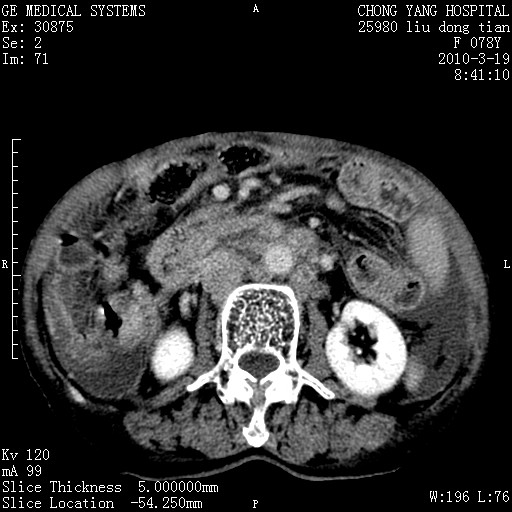

标题: CT25199:F 78Y 腹胀半年 消瘦乏力 [打印本页]

胆囊壁增厚并明显强化,胆囊癌伴多发转移瘤可能性大,淋巴瘤不除外,右肾囊肿,胸腹水.

考虑nhl,肝、脾、腹膜腔及腹膜后多发淋巴结受侵,腹水,右肾囊肿,慢性胆囊炎,右侧少量胸腔积液。

首先考虑恶性淋巴瘤 。

胰头有肿块形成,胰头ca伴肝脾、腹膜腹膜后转移

胆囊有软组织影有强化,支持胆囊癌,肝脾、腹膜后淋巴结转移。

nhl的淋巴结多围绕主动脉,而且主动脉会移位,所以不考虑nhl。

分开来讲:肝左叶、尾叶病灶有不均强化像肝癌;

脾脏病灶无强化,像多发囊肿或淋巴管瘤,不除外淋巴瘤(低强化);

胆囊增生性病变:胆囊癌,腺肌增生症,慢性胆囊炎;

肝门、胰腺头、腹膜后多个团块: 淋巴瘤,转移;

腔静脉肝内段细小有无布加可能?

一元论最好了 淋巴瘤所致改变; 胆囊癌转移不像,胆囊周围肝组织清晰,肝癌淋巴结转移?三元论都不止。

脾脏病灶像车轮 莲花,第一感觉还像包虫呢。真想全切出来一个个做病检。

胰头ca伴肝脾、腹膜腹膜后转移!

最后报的胰头癌多发转移,脾脏单独考虑囊肿或淋巴管瘤。